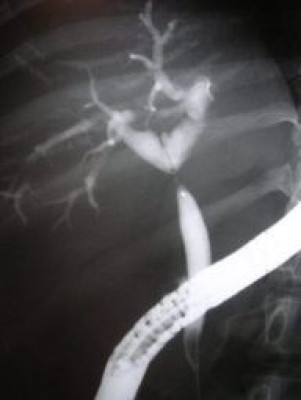

Colagiopancreatografía Retrógrada Endoscópica (ERCP)

Envíado por Gastroclínica